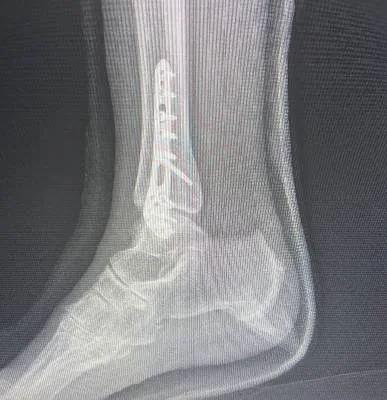

I had surgery with Dr. Haytham, and I’m very happy with the results. He previously operated on my leg after a fracture, and that surgery was very successful. Recently, I had another surgery on my knee, which was done in the simplest and most professional way. After the operation, I was able to return to my normal life — I can play football and be active again after a long time of not being able to. Dr. Haytham and his team took great care of me throughout the process, and I truly thank him for his excellent work and dedication